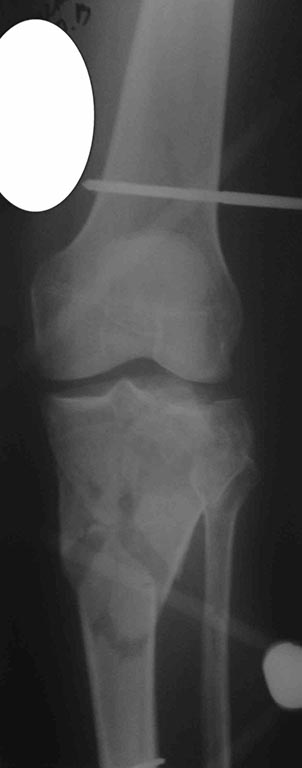

[Ortho] перелом проксимальной тибии + вывих бедра

сегодня только такое